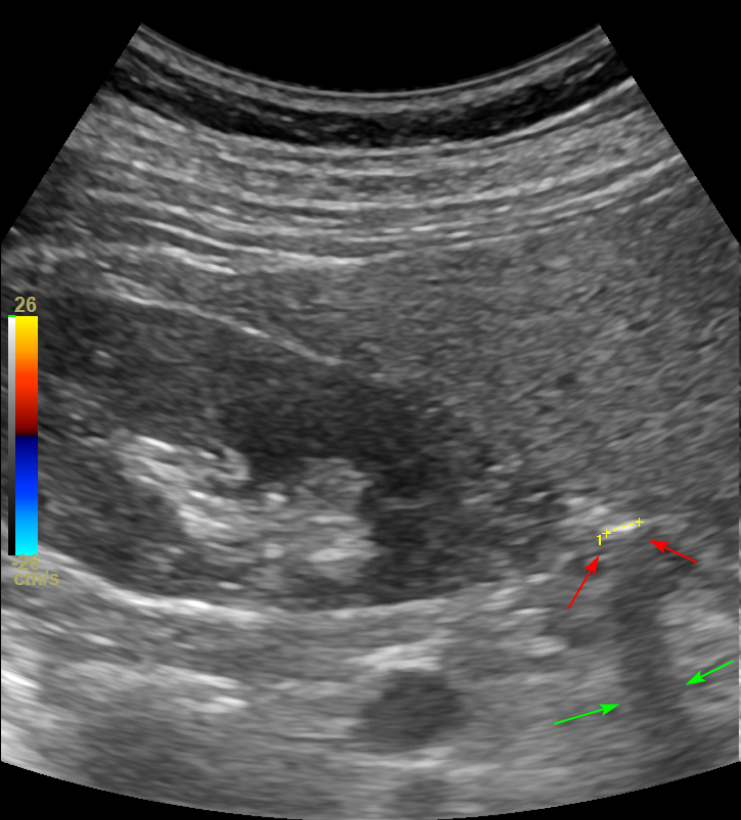

한의학의횡문 지실혈쪽

그러니까 위쪽 허리에는

신장(콩팥, Kidney)이라는 장기가

매우 가깝게 위치하거든요

이 환자분은 신장 주변에서

그림자**(녹색 화살표)와 초음파가 통과하지 못한 딱딱한 흰색 선**(빨간 화살표)이

보입니다.

요로 결석이 의심되어

신장쪽을 두들겨 타진해보니

최근 아프던 통증이

똑같이 나타납니다.